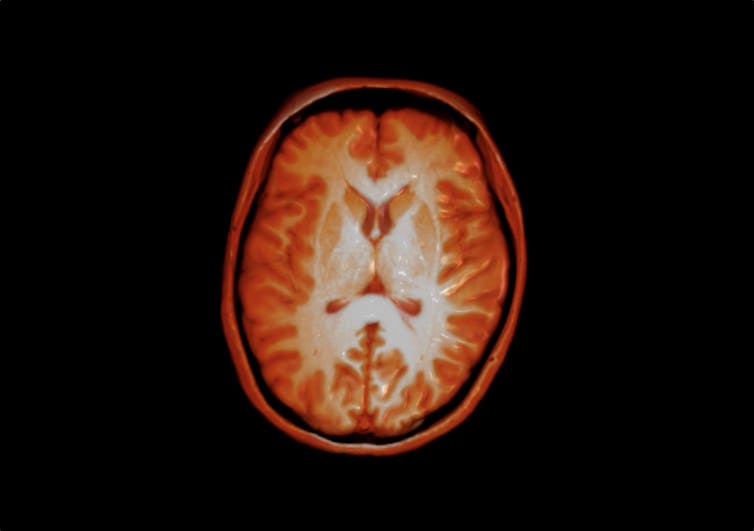

© Dr Flavio Dell’Acqua, CC BY